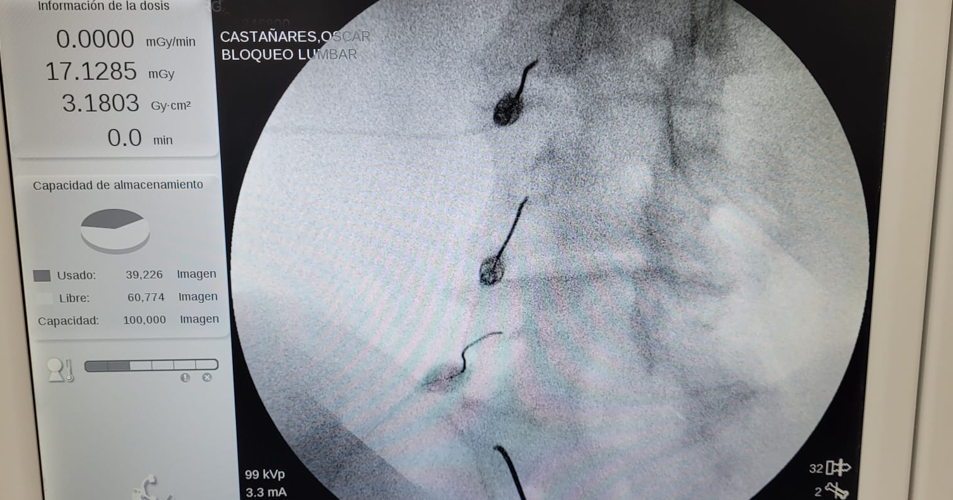

Para su tratamiento en TIDOL, se le realizó una radiofrecuencia facetaria con bloqueos a nivel de L5 S1. Luego del tratamiento, el paciente retomó su actividad física deportiva con una intensidad del dolor nula.